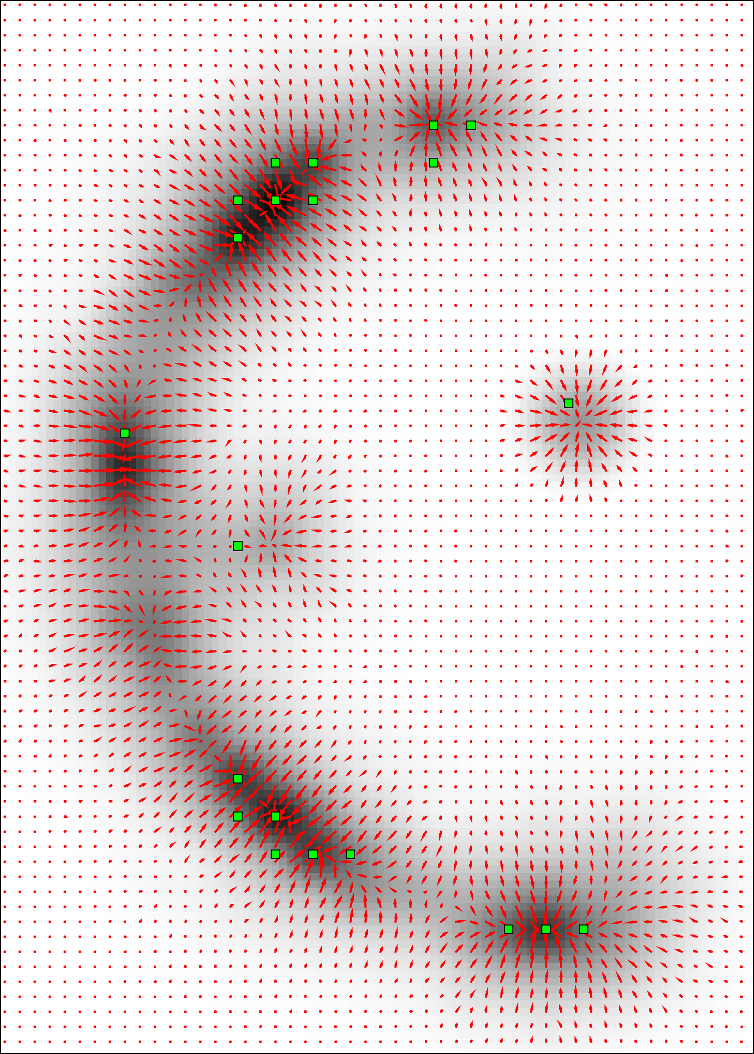

, , and modulate the respective components of the canonical Laplacian of Gaussian () filter oriented along the principal directions of . It is clear that given any arbitrary orientation as an orthonormal basis similar to , the proposed dictionary of filtering kernels can steer by computing the rotation transform, which maps the integral orientation basis of each Gaussian kernel on . Together with the SLoGS filtering kernel , we determine the second-moment matrix associated to the filter impulse response by adopting the ellipsoid model in the continuous neighborhood of . A symmetric tensor is derived from the eigendecomposition of as , where is the diagonal matrix representing the canonical unitary volume ellipsoid

the respective semiaxes’ lengths. Conversely from , which is indeterminate, the tensor field is a symmetric positive definite (SPD) matrix for any . Here, the definition of the tensor kernel in (4) can be further reformulated exploiting the intrinsic log-concavity of . By mapping , a convex quadratic form is obtained, so that is an SPD, as the modelled tensor . In either case, the manifold of tensors can be mapped into a set of 6 independent components in the Log-Euclidean space, which greatly simplifies the computation of Riemannian metrics and statistics. We refer to [3] for a detailed methodological description. The continuous and smooth tensor field inherits the steerable property. Similarly to diffusion tensor MRI, the kernel shows a preferred diffusion direction for a given energy potential, e.g. the scalar function itself (fig. 1). This allows to define an arbitrary dictionary of filtering kernels (DFK) that embeds anisotropy and high-order directional features to scalar curvilinear templates, which enhances and locally resembles typical, smooth vessel patterns. Together with the arbitrary SLoGS DFK, we also introduce an extra pair of non-curvilinear kernels for completeness. These are the pseudo-impulsive , an isotropic derivative filter given by the Laplacian of Gaussian of , representing a Dirac delta function for . Also, the uniformly flat is another isotropic degenerate case, where the Laplacian of Gaussian derives from , which is assumed to be a uniform, constant-value kernel for . The purpose of introducing the extra kernels is to better contrast regions that most likely relate to vessel boundaries and to image background, respectively. Although and have singularities, ideally they represent isotropic degenerate kernels. Therefore we associate pure isotropic tensors for any given , so that (Identity). The respective directional kernel bases are undetermined.

The idea is to convolve finite impulse response SLoGS with the discrete vascular image in a scale- and rotation-invariant framework, to obtain simultaneously the connected vesselness maps and the associated tensor field. For simplicity, the filtering steps will be presented for a generic scale . Scale-invariance is achieved by keeping the size of the small compact-support SLoGS fixed, while the size of the vascular image varies accordingly with the multi-resolution pyramid. Also, different will produce SLoGS kernels with different spatial band-pass frequencies. is down-sampled at the arbitrary scale as proposed in [7] to obtain . An early saliency map of tubular structures is then determined as

is derived from the discretized tubular kernel (fig. 1), whereas is defined as a group of orthonormal basis in , using an icosphere at arbitrary subdivision level to determine the orientation sampling in 3D. is meant to provide an initial, coarse, although highly-sensitive set of saliency features in : the vessel spatial locations and orientations. The identification of such features has two advantages; firstly it restricts the problem of the rotation-invariant filtering to an optimal complexity in 3D avoiding unnecessary convolutions; secondly it allows to use a locally selective overlap-add (OLA) [15] for the analysis/synthesis filtering. In detail, vessel spatial locations are mapped as voxel seeds , and the associated set of orientations forms a group of orthonormal basis in . We define as

where is the divergence of ’s gradient vector field, are the eigenvalue maps derived from the voxel-wise eigendecomposition of , and is the pth quantile of the positive samples’ pool. With , the orientations are automatically determined as the set of eigenvectors associated to . The greater the intensity threshold , the greater the image noise-floor rejection, the lower the number of seeds and the fewer the details extracted from . Also, the cardinality of and is a trade-off for the convolutional complexity in each OLA filtering step. The analysis/synthesis filtering can be embedded in a fully parallel OLA, by considering an overlapping grid of 3D cubic blocks spanning the domain of , and by processing each block so that at least one seed exists within it. The integral connected vesselness map , for each block at any given scale , has the form

Here, is the convolutional filter response given the considered SLoGS kernel. In detail, is the down-sampled image in , is the 3D OLA Hann weighting window, and is the steered filtering kernel along , those being the seeds’ orientations in . Note that in the discrete domain each voxel has a spatial indexed location . The anisotropic tensor field is synthesized and normalized in the Log-Euclidean space as the integral weighted-sweep of each steered tensor patch within the block , and has the form

where is the integral normalizing weight-map accounting for all vessel, boundary and background components; is the modulating SLoGS filter response at as in (7); is the steered Gaussian impulse response associated to the kernel ; is the Hann smoothing window in the neighbourhood centred at , and is one of the 6 components of the discrete steered tensors patch in the Log-Euclidean space. Note that all 6 tensorial components are equally processed, and that the neighbourhood and the SLoGS tensors patch have the same size. In (8), integrates also the isotropic contributions from vessel boundaries and background to better contrast the tubular structures’ anisotropy and to reduce synthetic artifacts surrounding the vessels (fig. 1). In particular, is averaged with an identically null tensor patch in the Log-Euclidean space in correspondence of boundaries and background, and is computed as in (7), where the image negative of is considered. Lastly, the connected vesselness maps and the associated synthetic tensor field are reconstructed by adding adjacent overlapping blocks in the OLA 3D grid for the given scale .